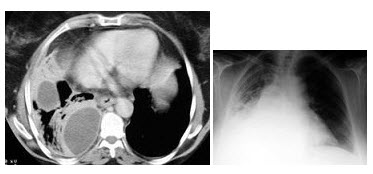

男,54岁,发热、胸痛1月余,继往有酗酒史,结合CT图像,最可能的诊断是()

A、脓胸

B、肺脓肿

C、大叶性肺炎

D、肺囊虫病

E、肺癌

A